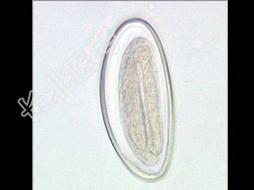

- 单项选择题关于检查图中所示的蛲虫卵的描述,错误的是 ( )

A、检查时间在早晨起床前,未解大便前,清洗肛门之后

B、通常采用在肛门周围刮取物镜检

C、粪检虫卵阳性率低

D、连续检查3~5次,检出率达100%

E、常用的方法有透明胶纸肛拭法和湿拭法